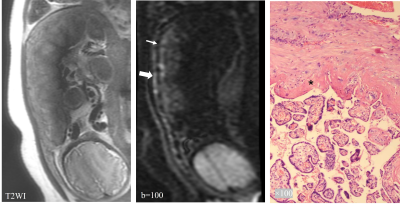

In the original IVIM images with b values of 50-600, the three-layer structure of the placental margin was shown (Figure 2). Combining all the cases in this study, b values between 50-200 could be shown clearly. When b=0, the three-layer structure was not displayed, and when b>200 the three-layer structure were not shown clearly due to image deformation.

Figure 2. In the original IVIM images with b values of 50-600, the three-layer structure of the placental margin was shown.